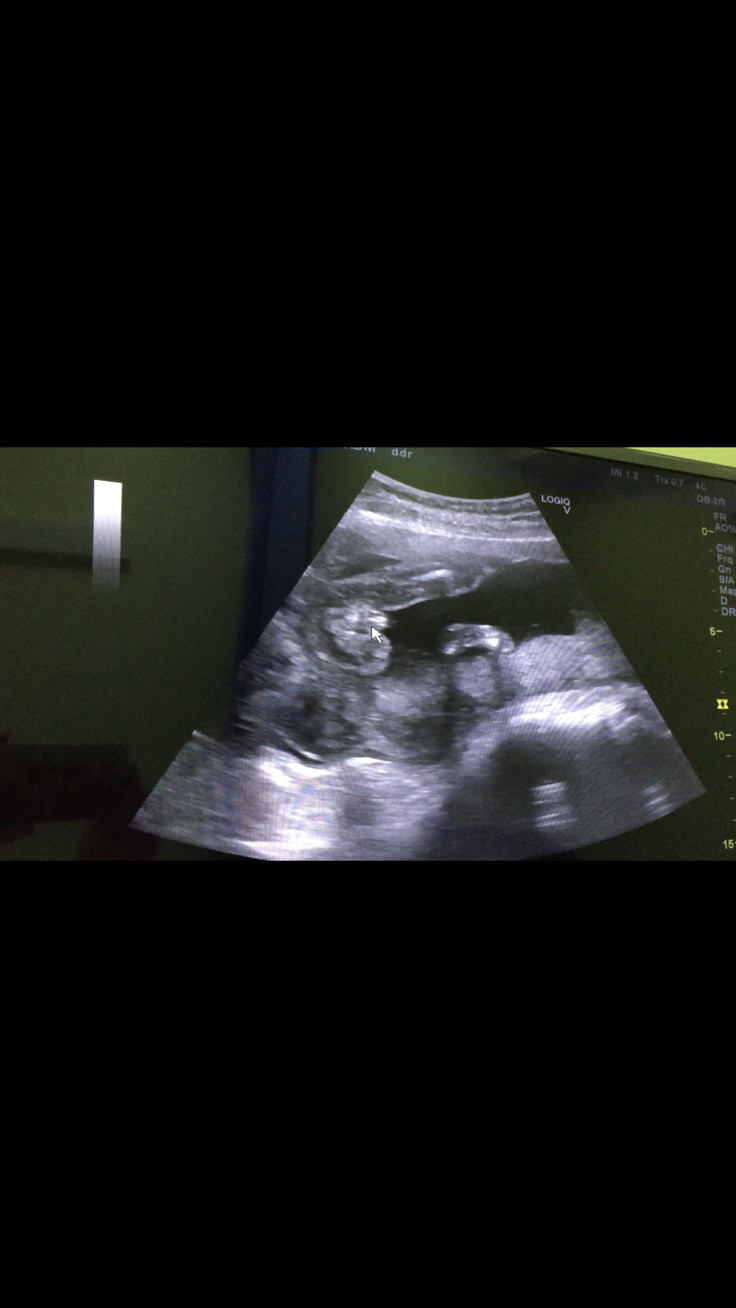

ผญ. ค่า😊 ในรูป5เดือน ตอนนี้6 แล้วหมอว่าผญ. 100% กลีบมาเยอะ😆